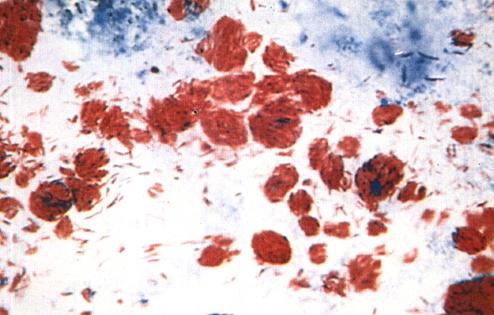

一、麻风杆菌的一般特征(图1-1a)

图1-1(a)

ML经萋-尼氏(Ziehl-Neelsen)抗酸染色法(简称Z-N法)染色在光学显微镜下可看到菌体被染成红色,呈直或略弯曲的杆菌,长1~8微米,宽0.3~0.4微米。ML无鞭毛、无芽孢,至于有无荚膜的问题,至今仍有争论

(一)染色特点

ML对抗酸染色、革兰氏染色均呈阳性。前者称为ML的抗酸性,这不是指ML有抵抗酸性物质的能力,而是指在用Z-N法染色时,ML能被石碳酸复红染成红色,着色后在规定条件下不能被酸性溶液(或酸醇溶液)脱色的现象。这种抗酸性可经新鲜、纯净的吡啶提取(2小时)而丧失,也可经过碘酸处理而恢复。Convit认为这是ML独有的,是鉴定ML的重要标准之一。我国吴勤学氏支持Convit的观点。